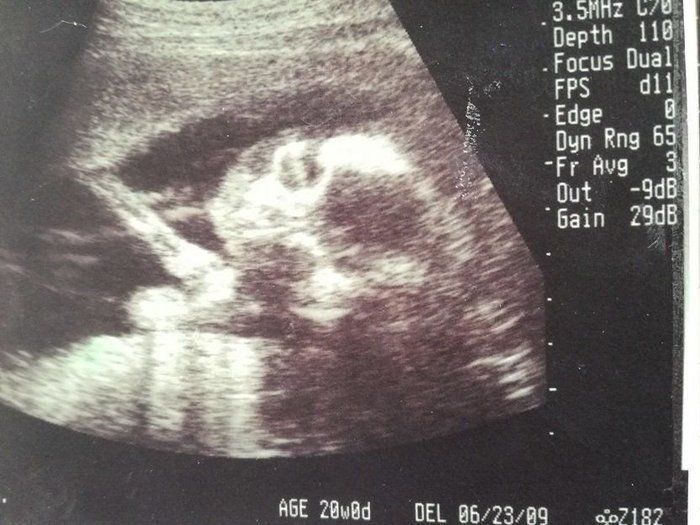

チャーミー小結さんの妊娠20週目のエコー写真

妊娠20週目の2D画像。横になった姿勢で、顔のアップの左側に写っている顎の細さが分かりました。赤ちゃんの推定体重345g。私の腹囲は人生初の90cm台になり、どこからみても貫禄充分なお母さんでした。